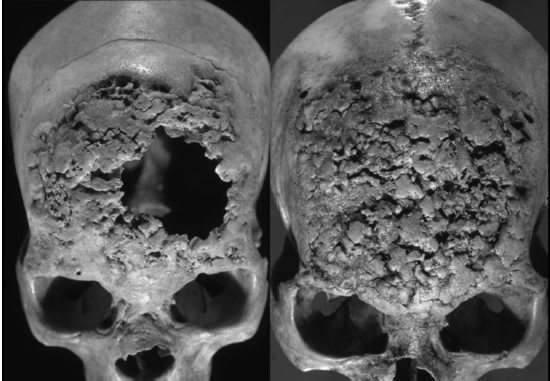

La evidencia bioarqueológica de treponematosis hallada en contextos prehispánicos y coloniales de México ha sido extensamente documentada e investigada [Mansilla et al. 1995, 2005; Márquez et al. 2015; Molto 2005; Salas 1982]. Mansilla y Pijoan [2005] analizaron las colecciones esqueletales de nueve sitios arqueológicos de varios estados de México datando del 900 a. C. hasta el 1520 d. C.. Este estudio demostró la presencia de treponematosis en el México prehispánico y encontró que las presentes enfermedades incrementaron en frecuencia a partir del 1000 d. C. Algunos de los ejemplos más notables de enfermedades treponémicas fueron encontrados en individuos excavados en la cueva de la Candelaria en Coahuila (1100-1300 d. C.) [Pineda et al. 2009]. En este sitio se recuperaron 116 cráneos, de los cuáles 60 presentaban lesiones líticas con formación de hueso reactivo en la bóveda craneal. Además, dos de los 60 cráneos también presentaban caries sicca, una lesión patognomónica de la infección treponémica [Pineda et al. 2009] (figura 3).

Antes de la destrucción del elemento óseo, éste debe ser documentado rigurosamente, especialmente si contiene marcadores informativos de algún proceso biológico, patológico o cultural (figura 4). Esta documentación debe incluir un registro fotográfico, descripciones macroscópicas, mediciones de longitud y peso, también se pueden tomar escaneos 3d o producir moldes de los elementos óseos para preservar sus características morfológicas. Toda esta información debe ser almacenada en una base de datos asociada al estudio, la cual debe ser accesible a los investigadores y a las instituciones custodias de los restos, como museos, universidades, osteotecas o gobiernos tribales (figura 5).